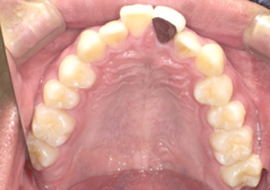

症例5

Before

After

| 主訴 | 上下3-3の並びが気になる |

|---|---|

| 年齢 | --- |

| 治療 期間 |

約1年 |

| 治療 内容 |

インビザライン5-5 |

| 治療費 | ¥517,000(税込)/調整料含む |

| 治療のリスク | 奥歯を動かさないので、前に出して並べていく。 歯と歯が移動するスペースを作るので、知覚過敏の症状がまれにでる。 歯を動かすことで、歯茎が下がるリスクある。 矯正終了後は、リテーナーを使用し、後戻りを防ぐ必要がある。 |